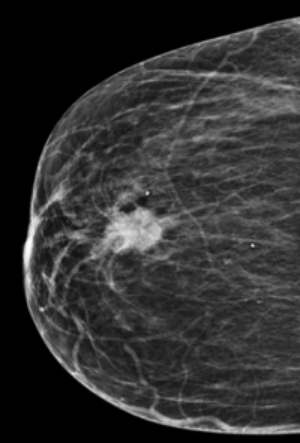

• formaţiune palpabilă la nivelul unui sân (Fig.1,2);

Fig. 1

Fig. 2